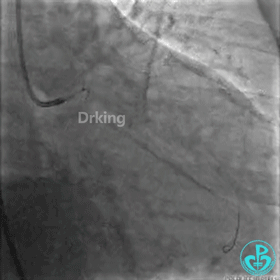

7F EBU指导导管到达左冠开口,把Sion导丝送至LAD远段,先后在微导管、双腔微导管、抽吸导管及2.5×20mm、3.0×15mm球囊堵闭LAD开口等各种技巧辅助支撑下,尝试Sion、BMW、Intuition、XT导丝反复塑形调整均未能通过LCX近段扭曲处送至远段。其间采用了球囊锚定、双腔微导管支撑、抽吸导管支撑、导丝塑成天鹅颈形状等技术。

经反复尝试失败后,发现由于LAD血管较粗,且LCX严重扭曲角度刁钻,而且不止一个高度弯曲(2处),以上技术实施时预进入LCX的导丝仍然会被弹入LAD。